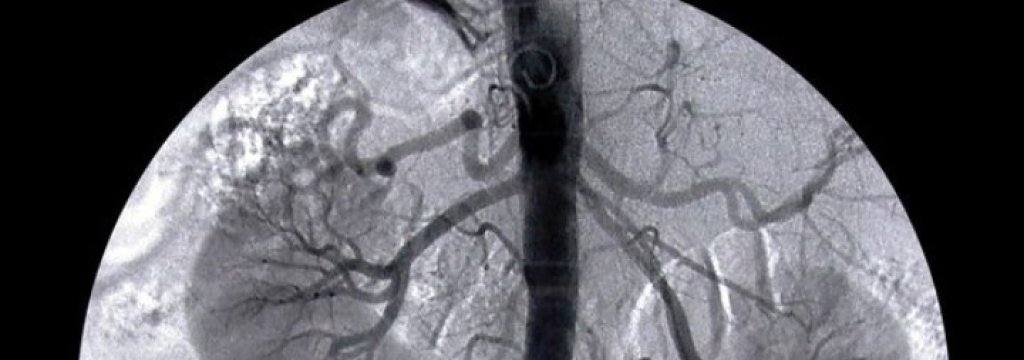

Калиевият фосфат е коварна сол, наслояванията й увреждат кръвоносните съдове, плацентата и пикочния мехур. Но мъжете страдат от калциеви камъни по-често от жените. Учените дълго време търсели обяснение на този факт. Специалисти от редица руски изследователски центрове стигнали да извода, че за образуването на калциево-фосфатни пластинки спомагат нанобактериалните инфекции.

Нанобактериите били открити в края на 20 век. Те могат да се видят само с помощта на електронен микроскоп. Тези микроорганизми ги обединява в една група техните размери, а не свойствата, които са слабо изучени. Със сигурност е известно само това, че нанобактериите участват в отлагането на калций в организма. Анализът на калцифицираните тъкани постоянно открива присъствието на нанобактерии в тази участъци. Според изследователи, тези бактерии могат да се предават по полов път, като при мъжете рискът за образуване на камъни в бъбреците е по-голям. Участникът в научната група, докторът на биологическите науки Полина Шварцбурд обяснява: